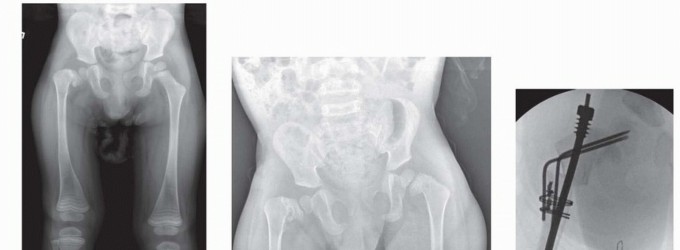

## Progressive anterior bowing of the long bones is quite common, especially in children with moderate to severe involvement, even with early treatment with bisphosphonates (FIG 1).

## FIG 1 • A. Radiographs of an infant with moderately severe OI, with the typical anterolateral bow most severe in the subtrochanteric region. B. At 16 months of age, bone strength is improved, but the deformity does not remodel.

## Radiographs of the lower extremity should be performed with the patellas directly anterior and also with the legs maximally externally rotated. This helps assess the severity of the disease, can help predict risk of fracture, and is useful in preoperative planning for osteotomies and instrumentation (FIG 2).

FIG 2 • Typical bowing deformity of the femurs and tibias caused by preexisting deformity and recurrent fractures is accentuated by the pull of the flexors, including the hamstrings and gastrocnemius-soleus complex. Note sclerosis in the medullary canal of the right tibia.